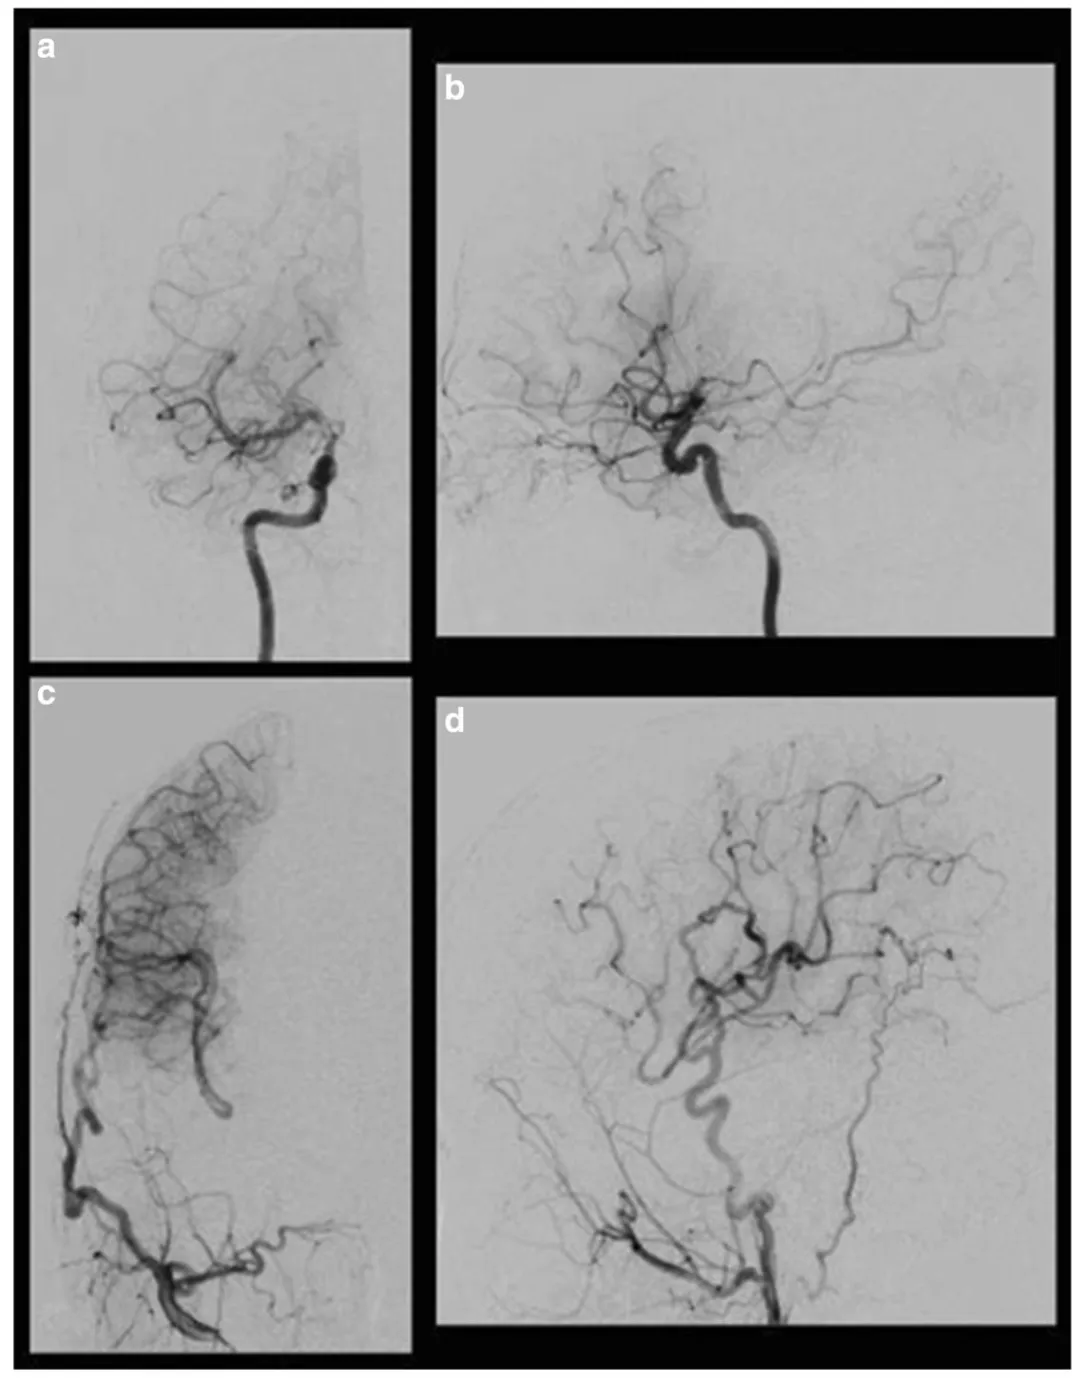

血管造影检查显示右侧颈内动脉末端狭窄,颅内出现典型烟雾状血管,疾病分期为铃木II期(早期),接近III期进展;左侧脑血管未见异常。XeCT(氙气计算机断层扫描)脑血流检查显示静息状态下脑血流量正常,乙酰唑胺激发试验后右侧大脑中动脉供血区脑血管反应性为14.8%。

手术过程顺利,术后患儿恢复良好,未出现手术相关并发症。术后长期随访显示头痛症状完全消失。术后7个月血管造影检查证实搭桥血管通畅良好,颈外动脉血流通过新建血管通路成功供应大脑中动脉及大脑前动脉供血区域。